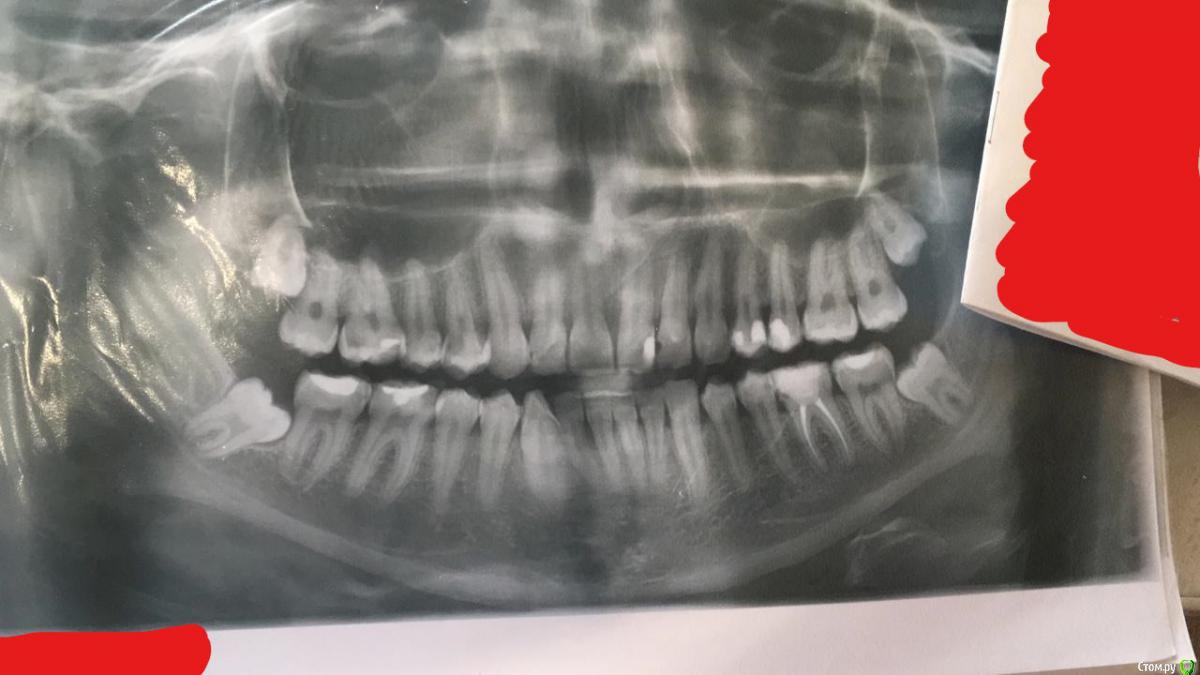

Dan666 Опубликовано 15 июня, 2020 Поделиться Опубликовано 15 июня, 2020 (изменено) Добрый день. Ситуация такая: врач говорит нужно удалять все 4 зуба мудрости. На снимке видно, что крайние зубы криво растут, но удаление сразу 4х зубов - решительный шаг, тем более что пока они мне не мешают. Поэтому хочу услышать мнение специалистов со стороны, нужно ли удалять зубы и есть ли возможность обойтись без удаления. Рентгеновский снимок прикрепил. Снимок сделан ~5 мес. назад. Кариес на других зубах уже залечили. Изменено 15 июня, 2020 пользователем Dan666 Ссылка на комментарий

Irouil Опубликовано 15 июня, 2020 Поделиться Опубликовано 15 июня, 2020 Да, нужно удалять все 4 1 Ссылка на комментарий

red_butler Опубликовано 15 июня, 2020 Поделиться Опубликовано 15 июня, 2020 + 1, удалять четыре Ссылка на комментарий

Dan666 Опубликовано 18 июня, 2020 Автор Поделиться Опубликовано 18 июня, 2020 Всем спасибо, завтра иду удалять первую пару. 1 Ссылка на комментарий